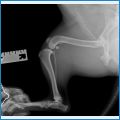

Вот рентгеновские снимки

Вот так выглядит пластинка на лапе спустя 28 дней после операции. Опороспособность восстановлена, но срастется кость только спустя 2 месяца и более. В данный момент на снимке уже образовалась "костная шишка", говорит о том, что кость срастается и отторжения импланта нет.

Вот второй снимок спустя 2 месяца после операции, возможно кому-то будет полезно. У песика всё хорошо срослось и он полностью готов к повседневным нагрузкам, ранее я его ограничивал во всем ,прогулках, играх, уменьшил рацион. Похудел за 2 месяца на 1 кг постепенно. Если кому нужны контакты хирурга оставляю здесь:

Фото рентгена через 1 мес. после операции. Рокки уже ходит и гуляет как обычно, нагрузки до 2-3 мес. только щадящие. Всё в общем отлично, не зря делали операцию. Бег и прыжки пока исключаем.